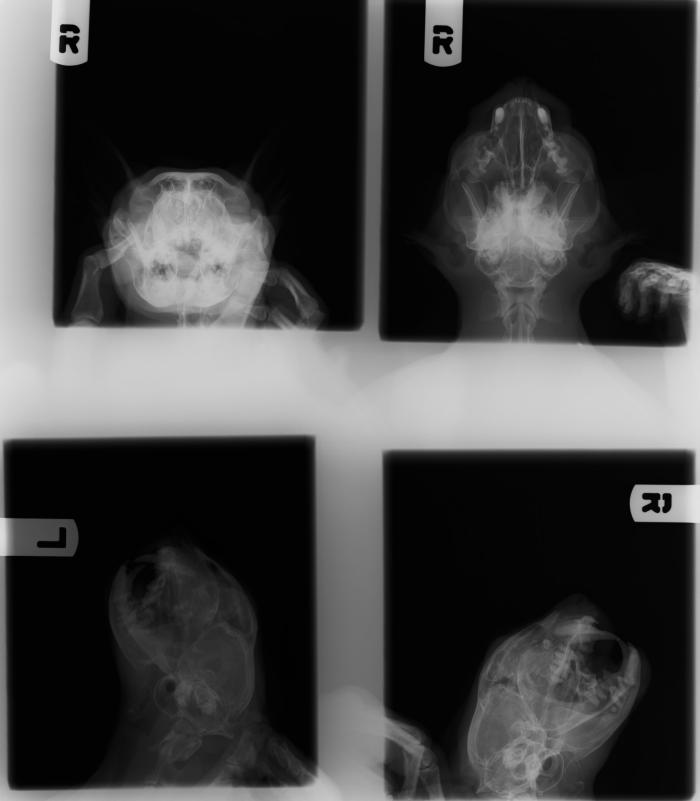

Estudio radiológico de cabeza (laterolateral derecha, ventrodorsal) y senos frontales (cráneo-caudal en flexión cervical): imagen compatible con fístula oronasal en área de pieza 204. En este momento no se aprecian alteraciones en los senos (Figura 4).